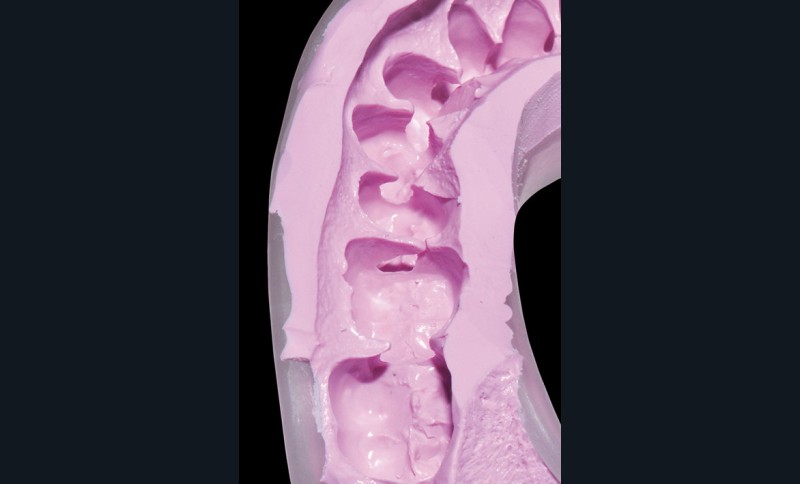

2. Une empreinte mandibulaire est réalisée à l’aide de 3M™ Imprint™ 4 Penta™ Preliminary pour obtenir une gouttière qui servira à la réalisation de la future prothèse transitoire.